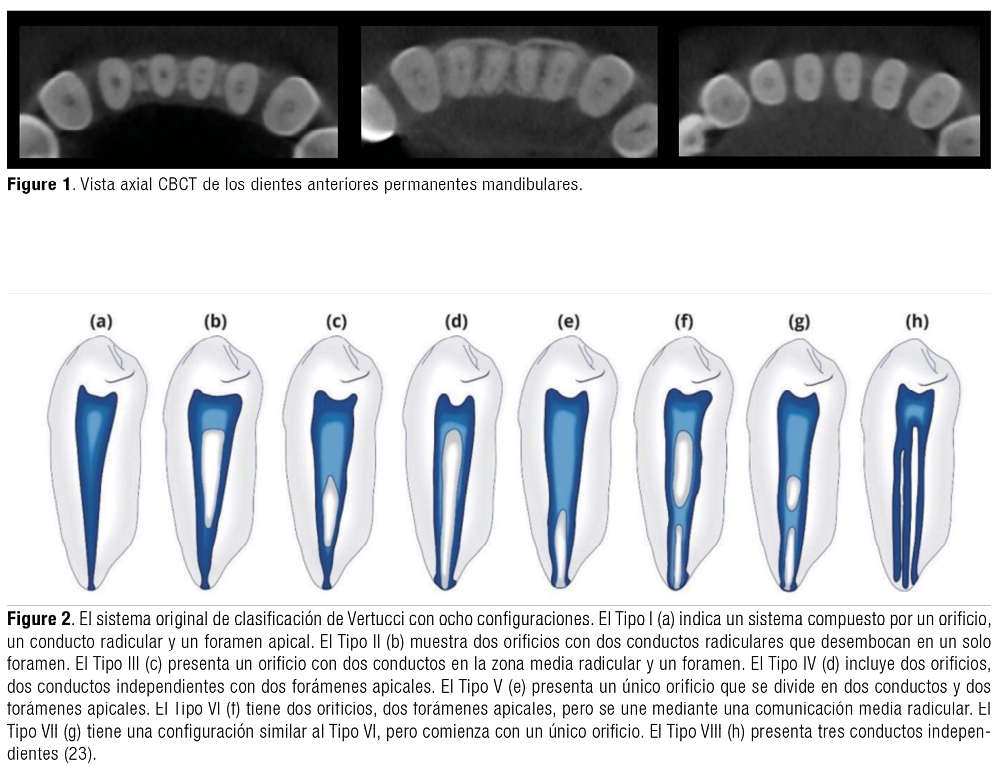

Por ello, existen sistemas de clasificación para relacionar la morfología del conducto radicular. En esta investigación se utilizó la clasificación de Vertucci, que clasifica la variación morfológica de los conductos en ocho tipos según la disposición de los canales desde la cámara pulpar hasta el ápice radicular, si bien es cierto es una clasificación muy conocida y utilizada, su limitación radica en que no proporciona el número de raíces ni un código único. En comparación, el nuevo sistema de clasificación de Ahmed et al., proporciona un código único para identificar el número de dientes, el número de raíces y la configuración del conducto, siendo esta una clasificación precisa y completa (17-20).

Se accedió a un total de 384 imágenes CBCT de pacientes a través de datos retrospectivos. Las muestras estudiadas fueron pacientes oriundos de Perú. Según Vertucci (Figure 2) y el nuevo sistema de clasificación de Ahmed (Figure 3). En la Tabla 1, se muestra la configuración de conductos según la clasificación de Ahmed y Vertucci cuyos resultados presentaron una mayor frecuencia en la clasificación ¹MI¹ y tipo I en el maxilar superior, seguidos de la clasificación ¹MI¹‐2‐¹ con el tipo III en el maxilar inferior, así mismo, se encontró dientes en la que se utilizó la codificación ¹MI¹‐²‐¹‐²‐¹, que fue un código único que se aplicó utilizando el último sistema introducido por Ahmed et al. Y este se observó en el canino derecho superior, el incisivo central derecho e inferior izquierdo, así como en el canino inferior izquierdo. El valor de chi cuadrado obtenido en el maxilar fue 0.016 y en mandibular fue de 0.001 cuyo valor es <0.05 lo que sugiere que hay relación estadísticamente significativa entre los dientes maxilares y mandibulares, así mismo, en la clasificación de Ahmed, el valor de chi cuadrado obtenido fue 0.001 en maxilar y mandibular, cuyo valor es <0.05 lo que sugiere que hay relación estadísticamente significativa entre los tipos de dientes maxilares y mandibulares y la clasificación de Vertucci.

Ahmed A., et al. (24), introdujeron una nueva clasificación con el objetivo de proporcionar un código único y preciso que permita a los profesionales de salud y estudiantes clasificar las configuraciones de las raíces y conductos radiculares. Al ser un sistema innovador, es más simple y didáctico para aquellos que deseen adquirir conocimientos sobre este nuevo sistema, lo que reduce los errores de clasificación en comparación con la clasificación de Vertucci. Esta última, que proporciona una categorización por “tipo” y presenta 8 clasificaciones diferentes, pero se limita en cuanto a su capacidad para abordar variaciones más complejas en la anatomía de los conductos radiculares, además al ser una clasificación antigua, puede no ser tan exhaustiva en cuanto a las anomalías del diente y no clasifica el número de raíces en comparación al nuevo sistema de clasificación de Ahmed, por esta razón, se han introducido nuevas categorizaciones para describir de manera más detallada la configuración de los conductos radiculares.